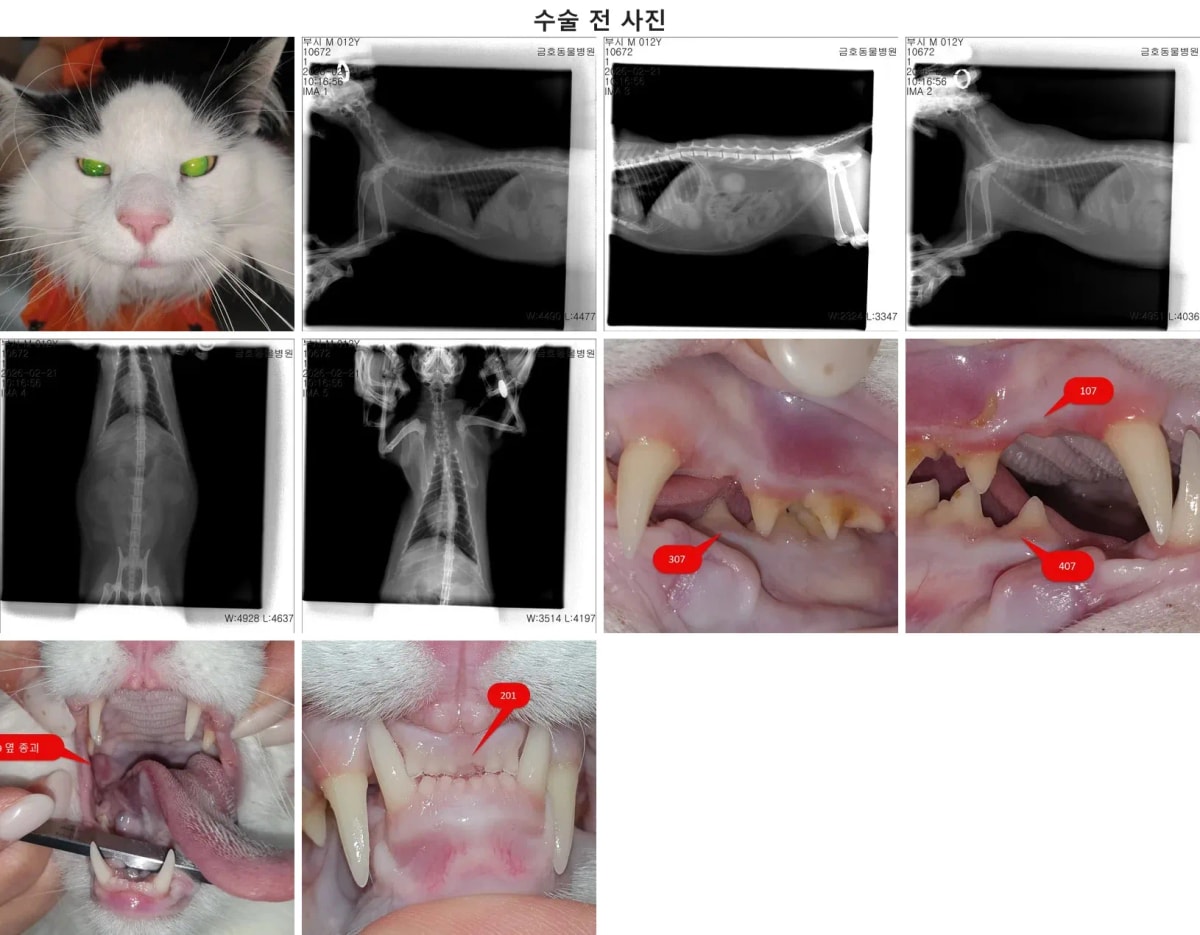

3. 수술 전 구강 엑스레이: 문제 치아 타겟팅

마취 후 진행된 정밀 구강 엑스레이 검사에서 부시의 구강 내 여러 문제점들이 구체적으로 확인되었습니다. 우측 상악 어금니(109번), 좌측 상악 어금니(209번)는 치주염(PD2 단계)이 진행 중이었고, 특히 우측 하악 어금니(409번)는 치주염과 더불어 잇몸뼈가 심하게 녹아내리는 치조골 소실(ABL2) 및 뿌리 분기부 노출(F2)이 확인되었습니다.

수술 전 정밀 구강 엑스레이 소견

또한, 좌측 상악 앞니(201번)는 겉으로는 이가 빠진 것처럼 보였으나 엑스레이 상에 부러진 뿌리(잔존 치근)가 남아있음이 밝혀졌습니다. 이처럼 엑스레이는 숨어있는 병변을 찾아내는 데 필수적인 과정입니다.

부시의 맞춤형 치과 수술 진행 과정

한편, 뿌리가 남아있던 201번 앞니는 현재 주변으로 염증 소견이 전혀 없어, 마취 시간을 연장하며 무리하게 턱뼈를 깎아내기보다는 정기적인 모니터링을 통해 지켜보기로 결정했습니다. 송곳니(204번) 역시 당장 시술이 필요치 않아 보존적 관리를 유지합니다. 수술 중에는 통증 제어를 위해 3부위에 걸쳐 국소 마취(신경 차단 마취)를 꼼꼼히 적용했습니다.